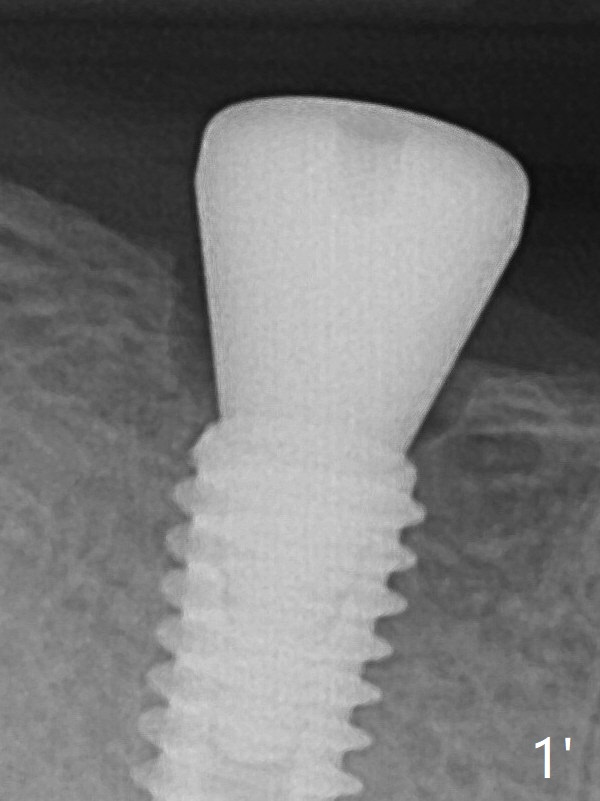

The female patient has limited mouth opening, complicated further by supraerupted opposing tooth. It is difficult to insert point drill and tap drill for #30 implant placement with guide. The former has to be inserted into the sleeve of the guide extraorally; two of them are placed intraorally together, while the tap drill is not used at all. When a 4.5x10 mm implant is placed, it is difficult to use #2 sensor to take PA. Finally a BW is taken with #2 sensor (Fig.1), while a PA is taken with #1 sensor (Fig.2). CT is taken to show clearance of the implant from the Inferior Alveolar Canal (Fig.3,4). To seat healing and later cemented abutments completely, a 5.5 mm profile drill is applied after implant placement; the outline is illustrated by red dashed line in Fig.1''. The elongated mesiolignual cusp of the tooth #3 has to be trimmed after placement of a 6x5 mm healing abutment. In fact trimming prior to osteotomy could solve the mouth opening partially. After removal of the 6x5 mm healing abutment, a 4.5x4(3) mm cemented abutment is incompletely seated (Fig.5 <) apparently due to proximity to the mesial crest (*). With reuse of a 4.6 mm profile drill, the abutment is fully seated (Fig.6), confirmed clinically by more clearance from the opposing tooth (Fig.7). Complete occlusal clearance is obtained by reduction of the opposing cusps without sensitivity since the tooth is nonvital (*). Return to No Deviation Xin Wei, DDS, PhD, MS 1st edition 05/28/2020, last revision 09/04/2020